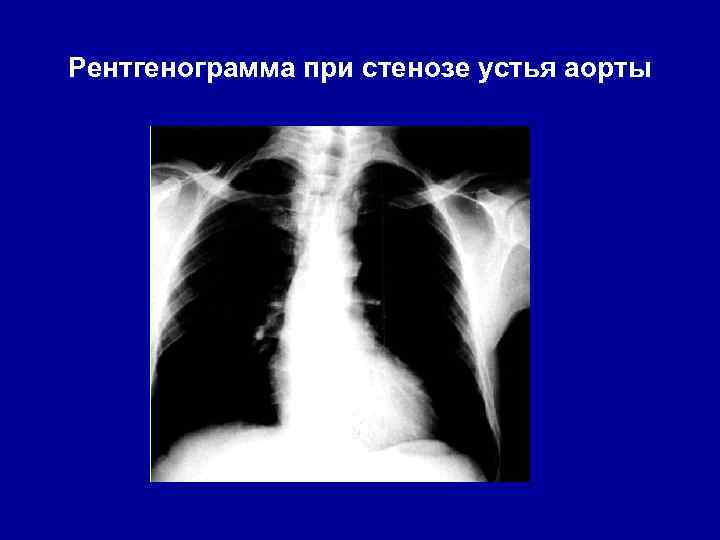

Рентгенограмма при стенозе устья аорты